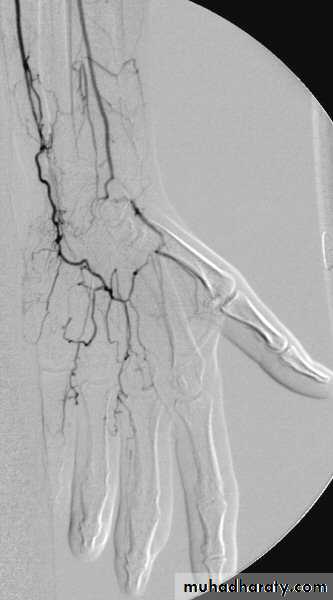

Angiography of hand vessels